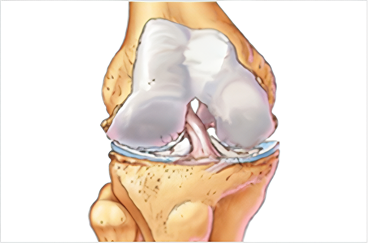

무릎 관절 속 반월연골판은 넙다리뼈(대퇴골)와 정강뼈(경골) 사이에 위치한 구조물입니다.

반월연골판 파열

연골판 조직은 고무처럼 탄력이 있으며 충격을 흡수하는 역할을 하지만, 노화로 인해 퇴행성 변화가 진행되면서 점차 딱딱하게 변성되기도 합니다.

이렇게 탄력을 잃게 되면 변성된 연골판은 큰 충격 없이도 일상생활 중에 손상되거나 찢어질 수 있습니다.

정상적인 반월상 연골판

파열된 반월상 연골판